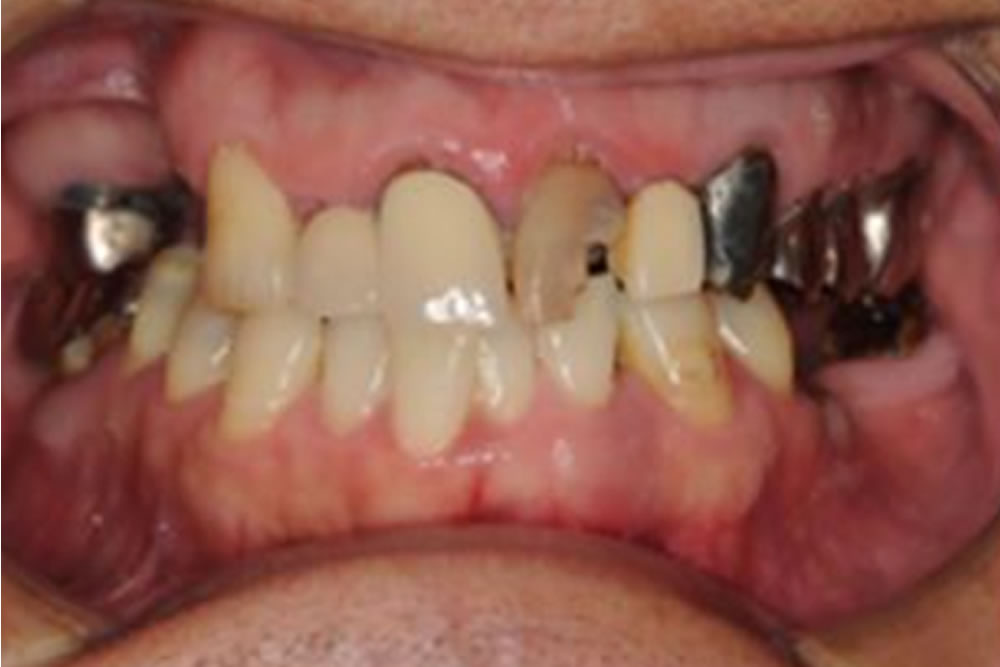

歯周組織再生療法・インプラント等を併用した症例

歯周組織再生療法・インプラント等を併用した症例 治療前 治療後 こちらの患者さまは、歯周病に加えて奥歯を失い、前歯の骨の支えもかなり少ない状態でした。11年前の歯科ドックで複数の問題が見つかり、一つひとつ丁寧に説明したう […]